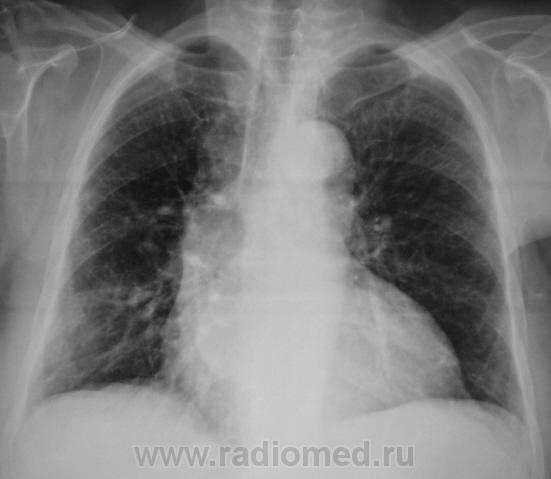

похоже в просет "что-то" растет, наверное показана бронхоскопия? А дополнительная тень не ушко правого предсердия?

Хорошие томограмы, жаль нет бочка посмотреть вентиляцию нижней доли, а так конечно в просвете бронха дополнительная тень, предсердие бы оттеснило весь бронх. Надо рекомендовать бронхоскопию.